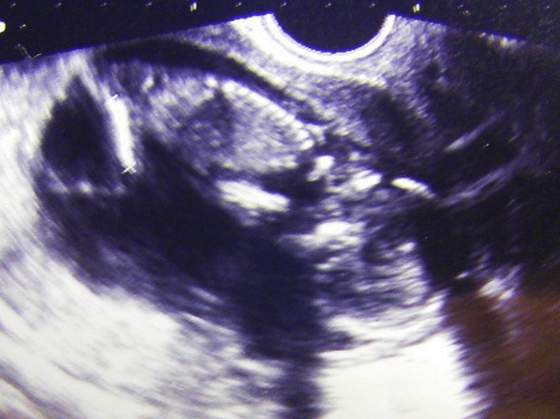

A oto efekt wczorajszego USG

Załączniki

• STH73284.jpg

STH73284.jpg

28,3 KB · Wyświetleń: 37

śliczna dzidzia

Paluszek piękna dzidzia będzie z tej kropki zobaczysz:tak:

Madziarka ale sliczna dzidzia ;-)))))))